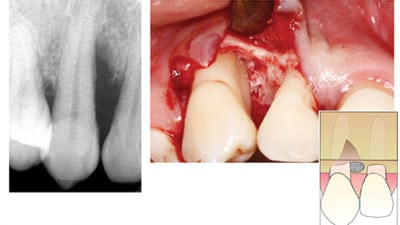

Improved Long-Term Treatment Outcomes of Teeth with Deep Pockets and Reduced Periodontal Support by Periodontal Regenerative Surgery

Introduction Periodontal regenerative medicine encompasses a spectrum of procedures that restore lost tooth-supporting hard and soft tissue, thereby reversing some of the damage caused by periodontal disease. This is in contrast with repair of periodontal tissues that was the staple of periodontal treatment for decades. Regenerative surgery involves the reflection of the gingival tissue and … Read more